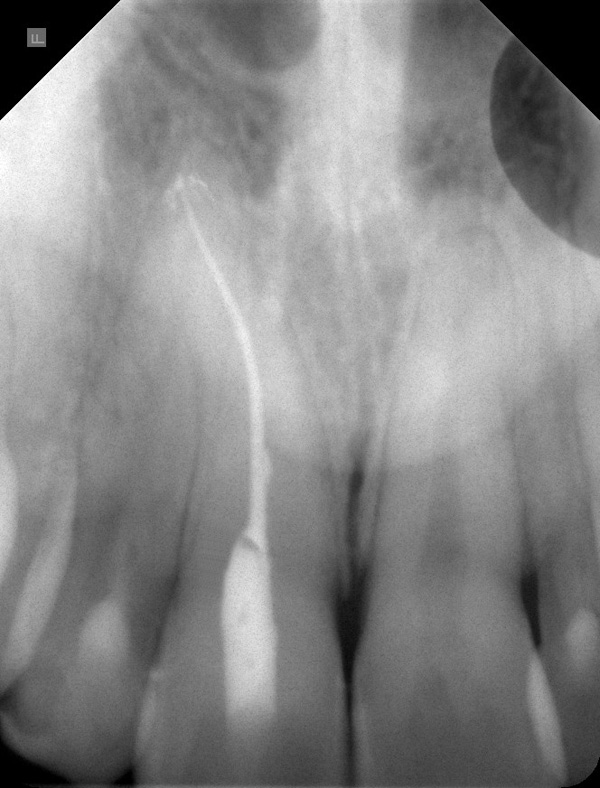

Das Ausgangsröntgenbild zeigt einen größtenteils obliterierten und mehrfach gekrümmten Wurzelkanal am Oberkieferfrontzahn 11. Der Zahn reagierte klinisch nicht auf Kälte und zeigte eine bräunliche, dunkle Verfärbung der gesamten Krone. Der Patient hatte seit 2 Wochen Schmerzen im Bereich der Wurzelspitze des Zahnes.

Ausgangsröntgen, stark gekrümmter und obliterierter Wurzelkanal: